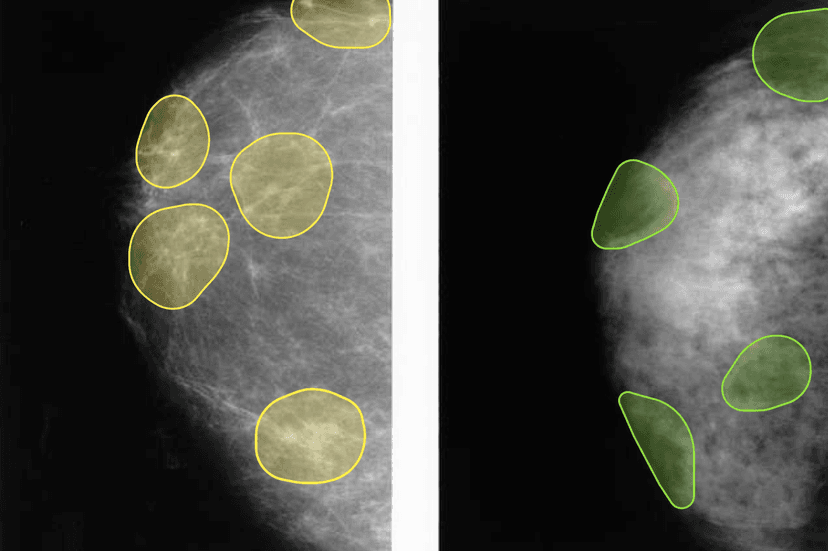

Mammography Analysis

Expert mammography annotation for breast cancer screening. Specialized in microcalcifications, masses, architectural distortions, and BI-RADS classification.

- •Microcalcification clustering

- •Mass detection and classification

- •Architectural distortion identification

- •BI-RADS categorization

- +4 more capabilities